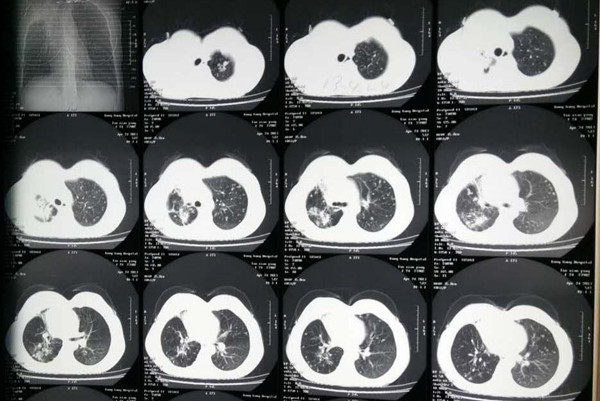

结核性胸膜炎是临床上比较常见的一个病症,对于该病的治疗目前主要还是依靠抗结核药物治疗,但是在这个治疗过程中,很多人会出现西药副反应,所以这个时候建议也可以选择中医来治疗,那么结核性胸膜炎中药怎么治疗呢,下面我们一起来看一下。

结核性胸膜炎在中医上是属于“肺痨”范围,基本的病机为肺虚卫弱,外邪侵袭。治疗原则标本兼治,从全局出发,让患者得到系统化的康复。